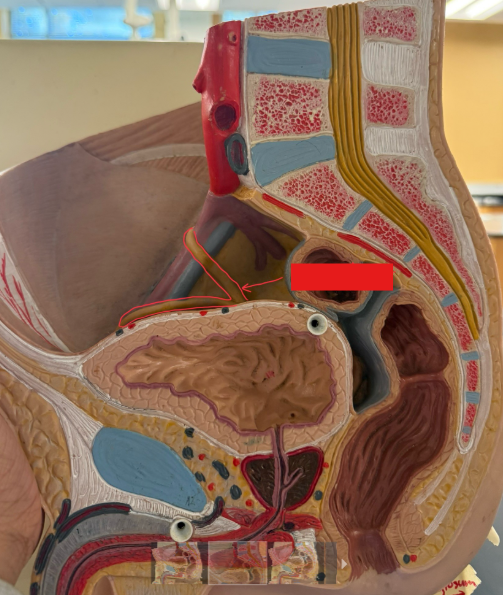

What is the name of the red box?

Ureter

What is the name of the red box?

Prostatic urethra